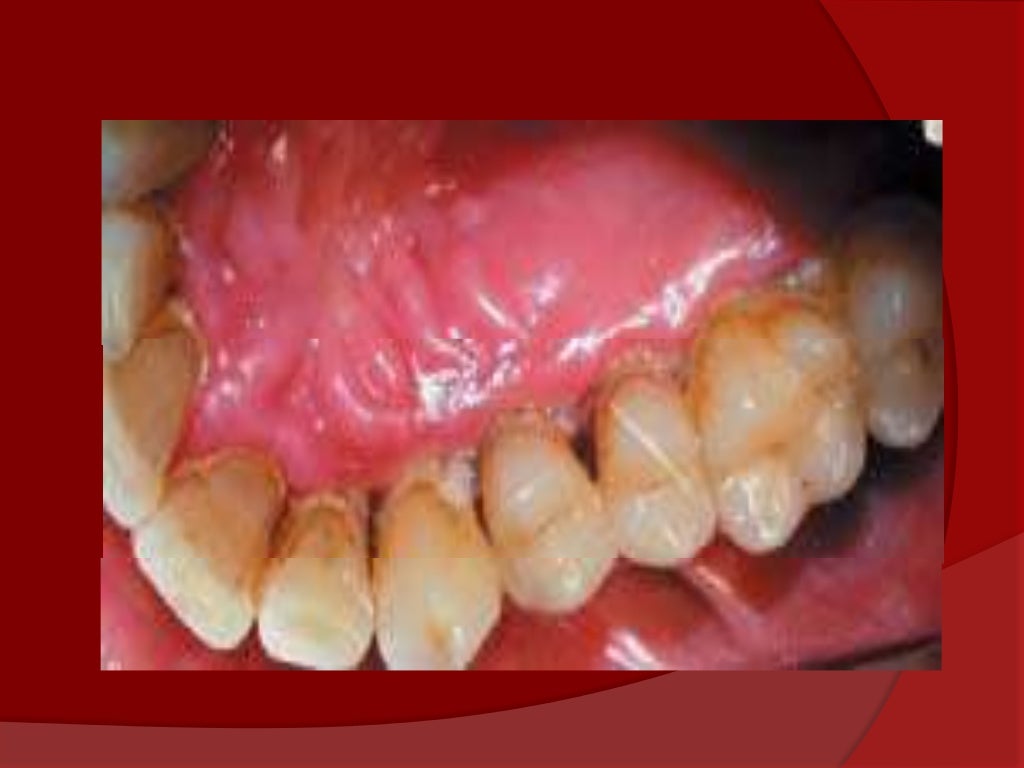

Gingivitis Necrotizante . Symptoms are acute pain, bleeding, and foul breath. Los síntomas son dolor agudo, sangrado y aliento de olor. Diagnosis is based on clinical findings. Treatment is gentle debridement, improved oral hygiene, mouth rinses, supportive care, and, if debridement must be delayed, antibiotics. La gingivitis ulcerativa necrosante aguda es una infección dolorosa de las encías. Acute necrotizing ulcerative gingivitis (anug) is a rare infectious disease of the gum tissue, affecting <1% of the population. Covers the management of acute necrotizing ulcerative gingivitis where the gums are acutely painful and swollen; The aim of this narrative literature review was to describe the available evidence on the diagnosis and treatment of ng, and present. Anug presents as an acute, painful, and destructive. They bleed easily and have. There are three major forms: It has an acute clinical presentation with the distinctive. Acute necrotizing ulcerative gingivitis is a painful infection of the gums. Necrotizing ulcerative gingivitis (nug) is a typical form of periodontal diseases.

Gingivitis Necrotizante La gingivitis ulcerativa necrosante aguda es una infección dolorosa de las encías. It has an acute clinical presentation with the distinctive. Diagnosis is based on clinical findings. They bleed easily and have. La gingivitis ulcerativa necrosante aguda es una infección dolorosa de las encías. Acute necrotizing ulcerative gingivitis is a painful infection of the gums. There are three major forms: The aim of this narrative literature review was to describe the available evidence on the diagnosis and treatment of ng, and present. Treatment is gentle debridement, improved oral hygiene, mouth rinses, supportive care, and, if debridement must be delayed, antibiotics. Anug presents as an acute, painful, and destructive. Symptoms are acute pain, bleeding, and foul breath. Covers the management of acute necrotizing ulcerative gingivitis where the gums are acutely painful and swollen; Los síntomas son dolor agudo, sangrado y aliento de olor. Necrotizing ulcerative gingivitis (nug) is a typical form of periodontal diseases. Acute necrotizing ulcerative gingivitis (anug) is a rare infectious disease of the gum tissue, affecting <1% of the population.